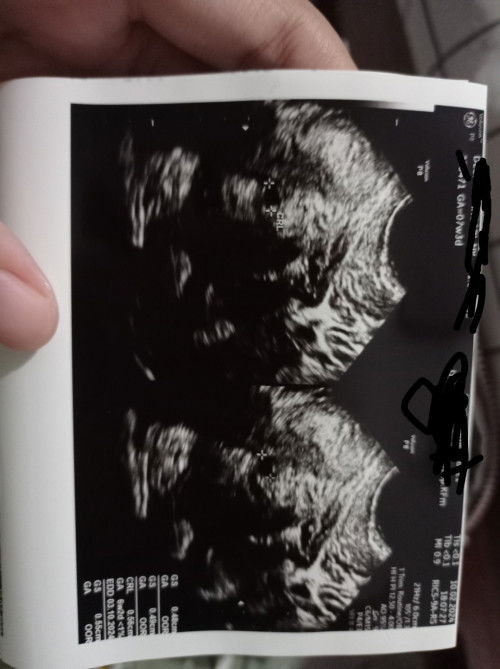

USG hamil, sudah terlihat kantung kehamilan. Tapi tespek negatif.